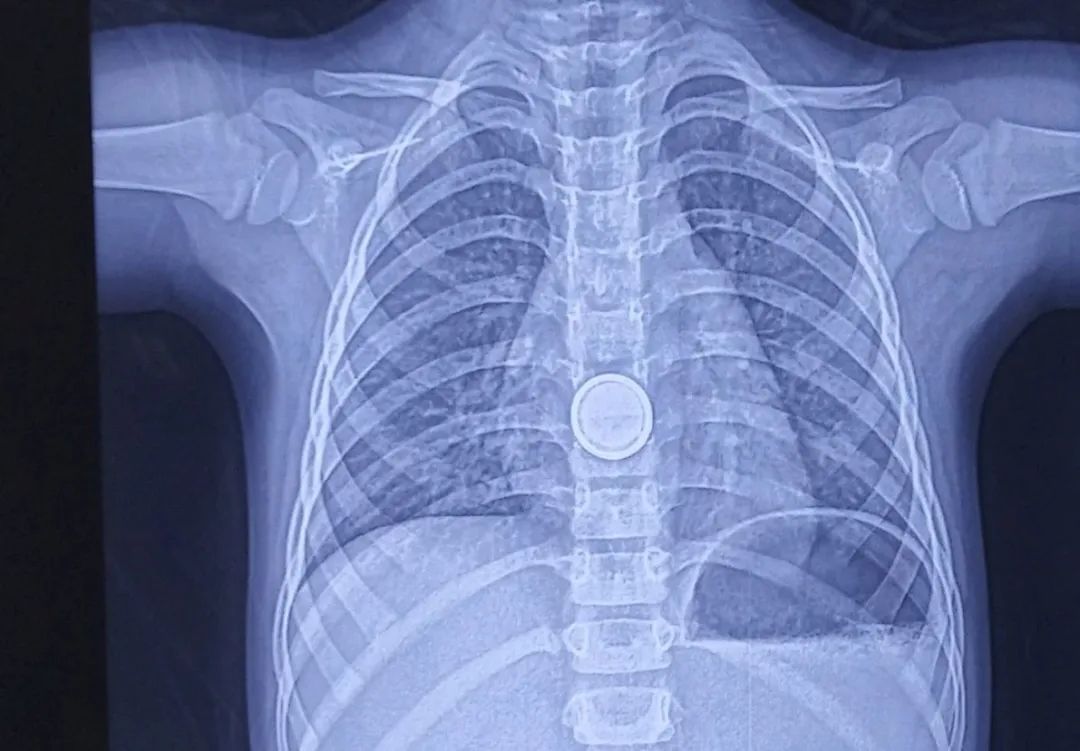

一个3岁小女孩,在家玩时吃下去一枚纽扣电池,电池嵌顿在小朋友的食管中段2个小时,食管受损严重,有穿孔的可能,我们立即放置了空肠营养管,避免饮食和胃内食物反流引起食管受损处发生感染。

唐都儿科内镜图